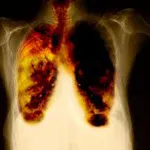

En ny behandling mod lungecancer bliver nu godkendt. Behandlingen er målrettet lungecancerpatienter med den særlige genmutationen EGFR og er mere effektiv sammenlignet med kemoterapi.

Det nye behandling - Iressa har vist sig at være mere effektivt end 2-stofs kemoterapi til behandling af patienter med ikkesmåcellet lungecancer, der har en såkaldt EGFR-mutation. Resultaterne stammer fra IPASS-studiet, som blev publiceret i online-versionen af det ansete tidsskrift The New England Journal of Medicine i onsdags.

Konklusionen på studiet er, at Iressa viser signifikant bedre resultater, når det gælder sygdomsfri overlevelse. Studiet viser samtidig, at patienter med ikke-småcellet lungecancer, der ikke har EGFR-mutation, bør have kemoterapi frem for Iressa.

Ud over den længere sygdomsfri overlevelse viser IPASS-studiet også, at patienter behandlet med Iressa oplever bedre livskvalitet og færre lungekræftsymptomer sammenlignet med patienter behandlet med 2-stofs kemoterapi. Desuden er der generelt færre bivirkninger med Iressa i forhold til kemoterapi.

Diagnosen lungecancer bliver stillet ved, at der foretages en vævsprøve af selve kræftknuden. Ved at foretage en yderligere analyse af vævet – en mutationstest – kan man vurdere, om patienten har en EGFR-mutation eller ej. Omkring 10-15% af alle lungecancerpatienter i Danmark har denne særlige gen-mutation.